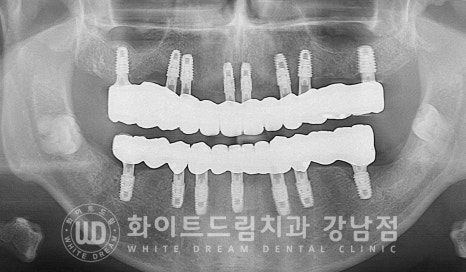

전체 임플란트 치료 전/후

동일 인물이며 동일 환경에서 촬영됨

치료 기간 : 24.01.11 - 24.07.02

40대 전체임플란트 치료

환자분은 5개월의 회복 기간을 가진 후 임플란트 보철 제작에 들어갔습니다.

이렇게 진행된 전체 임플란트 치료 기간, 얼마나 소요되었을까요?

환자분은 총 6개월 만에 잃어버린 씹는 즐거움을 되찾으시고

치료를 마무리하게 되었습니다.

40대 전체임플란트 치료 기간 : 24.01.11 - 24.07.02